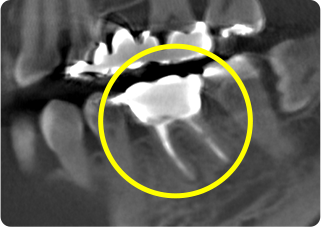

自家歯牙移植・精密根管治療・セラミッククラウン症例

術前

術後

| 主訴 | 奥歯の銀歯がぐらぐらして取れそう |

|---|---|

| 治療期間/回数 | 5ヵ月、10回 |

| 価格(税込) | 264,000円(税込) |

| リスク・副作用 | 生着不良、歯根吸収、骨性癒着の可能性 |

| ポイント | 銀歯の中でむし歯が進行し、保存不可能だったため抜歯し、後ろの親知らずを移植。移植の際に3Dプリンターで作製した親知らずのレプリカを使用し、治療時間の短縮と移植ポジションの確認を行った。生着するのを待ち、精密根管治療を行った後、セラミッククラウンを装着した。 |